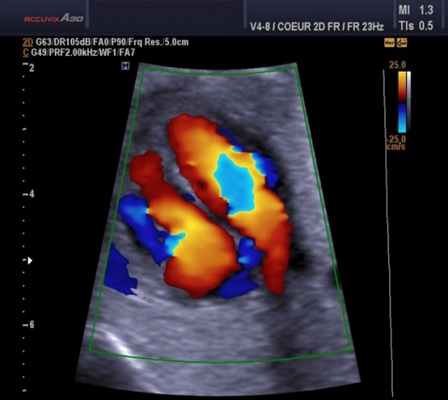

а) Недостаточное выявление потоков из-за проблем с чувствительностью. Многие записи цветовой допплер-ЭхоКГ из апикального доступа не содержат вообще или содержат довольно малоцветокодированной информации в области предсердий. Такое положение дел должно бы вызвать у исследователя критическое отношение к правдивости получаемой информации о потоках крови.

Пример неверной информации. На рисунке ниже слева показан подобный пример, создающий у исследователя впечатление, что у этого пациента с митральной недостаточностью во время систолы в области левого предсердия нет никакого антеградного потока. Однако кардиологу даже с умеренным знанием основных гемодинамических закономерностей известно, что в систолу и раннюю диастолу предсердия интенсивно наполняются из легочных вен и что при неискаженном допплеровском исследовании эти потоки в виде красной, антеградной цветокодированной зоны должны занимать не менее 70% левого предсердия.

То, что часто мы этого не видим, связано с касающимися всех ультразвуковых систем проблемами чувствительности по определению потоков на большой глубине. Но если даже нормальные антеградные потоки не могут быть визуализированы, то это же, к сожалению, относится и к патологическим потокам, диагностике которых и должно бы служить ультразвуковое исследование.

Слева: пример исследования в режиме цветовой допплер-ЭхоКГ (четырехкамерная позиция), где отсутствует информация о потоках крови в области предсердий у пациента с дилатационной кардиомиопатией и митральной недостаточностью.

Справа: после контрастного усиления, благодаря которому визуализируется как патологический (большая струя регургитации), так и нормальный антеградный кровоток (красный цвет).

На рисунке ниже справа показано изображение того же пациента: при контрастном усилении допплеровское исследование выявляет широкую, проходящую через все предсердие струю митральной регургитации наряду с ангеградным ламинарным потоком. То, что контрастное усиление не ведет к искажающему увеличению струи регургитации, было доказано при сравнении этого режима с чреспищеводным неконтрастированным допплеровским исследованием, и это позволяет достичь существенно более надежной оценки степени тяжести митральной недостаточности.